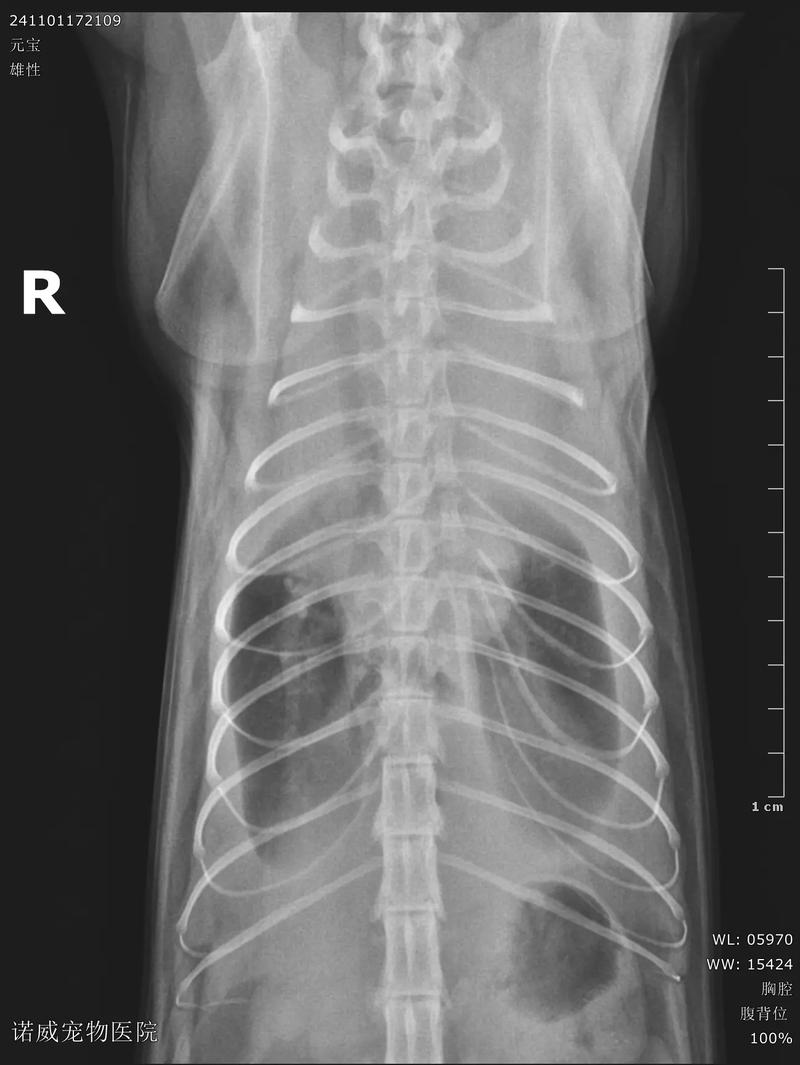

〖Three〗、猫咪胸腔积水是有救的,但是需要注意以下问题,第一:胸腔积水是由于受外伤、器官病变等导致胸腔渗透压的改变,使循环中的体液聚集在胸腔,会严重影响猫咪呼吸和心跳。第二:需要进行X光检查确诊胸腔积水的具体情况,此外再进行手术治疗,术后输液比较好添加白蛋白。